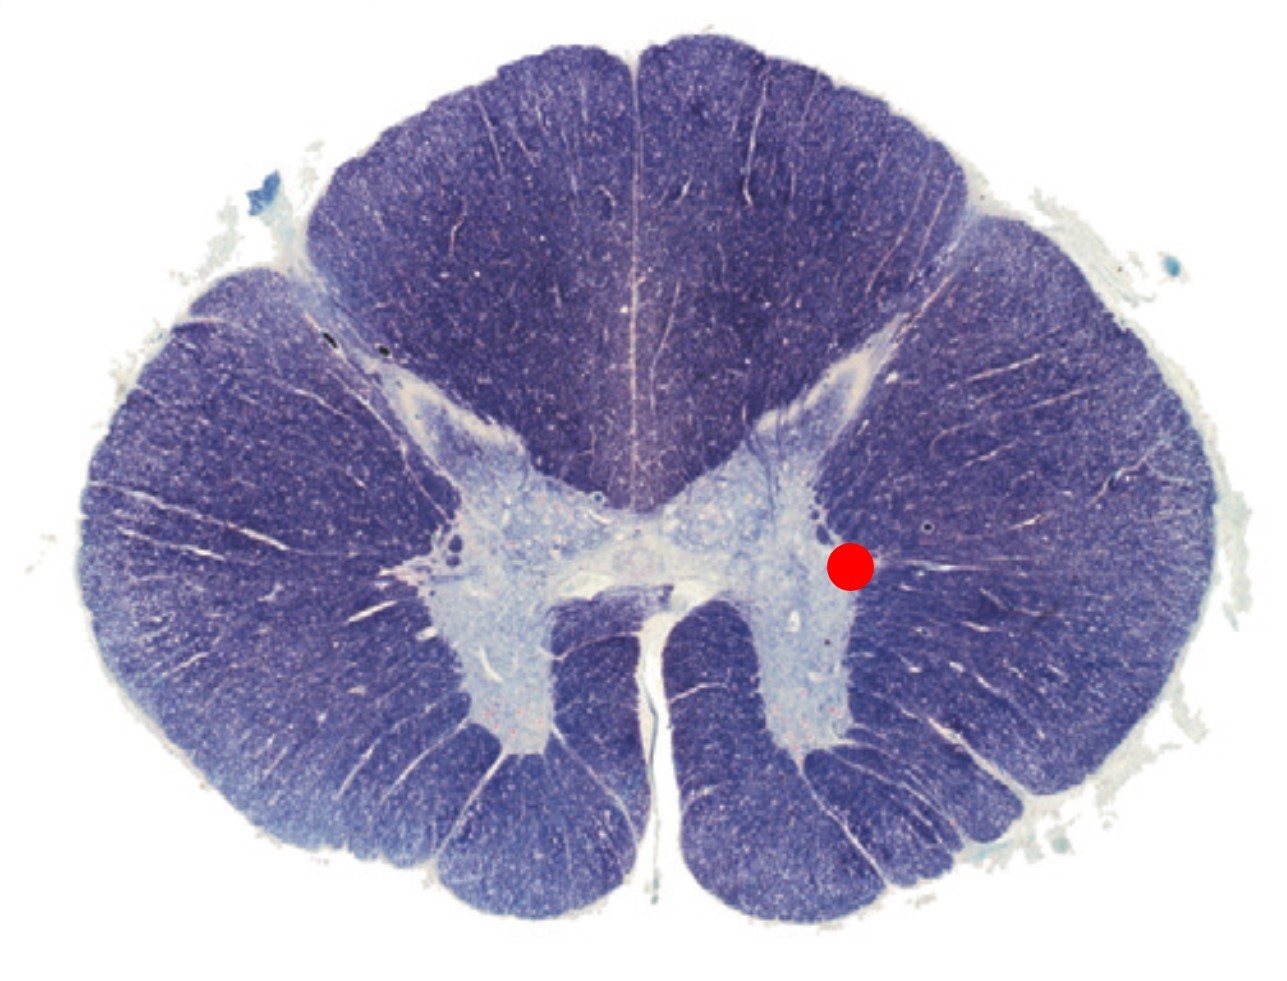

The cross section corresponds to which level of the spinal cord:

Thoracic

The dorsal aspect of the spinal cord below T6 is characterised by how many columns?

2

This region of the spinal cord contains all of the following EXCEPT:

cuneate fasciculi

gracile fasciculi

lateral horns

Lissauers tract